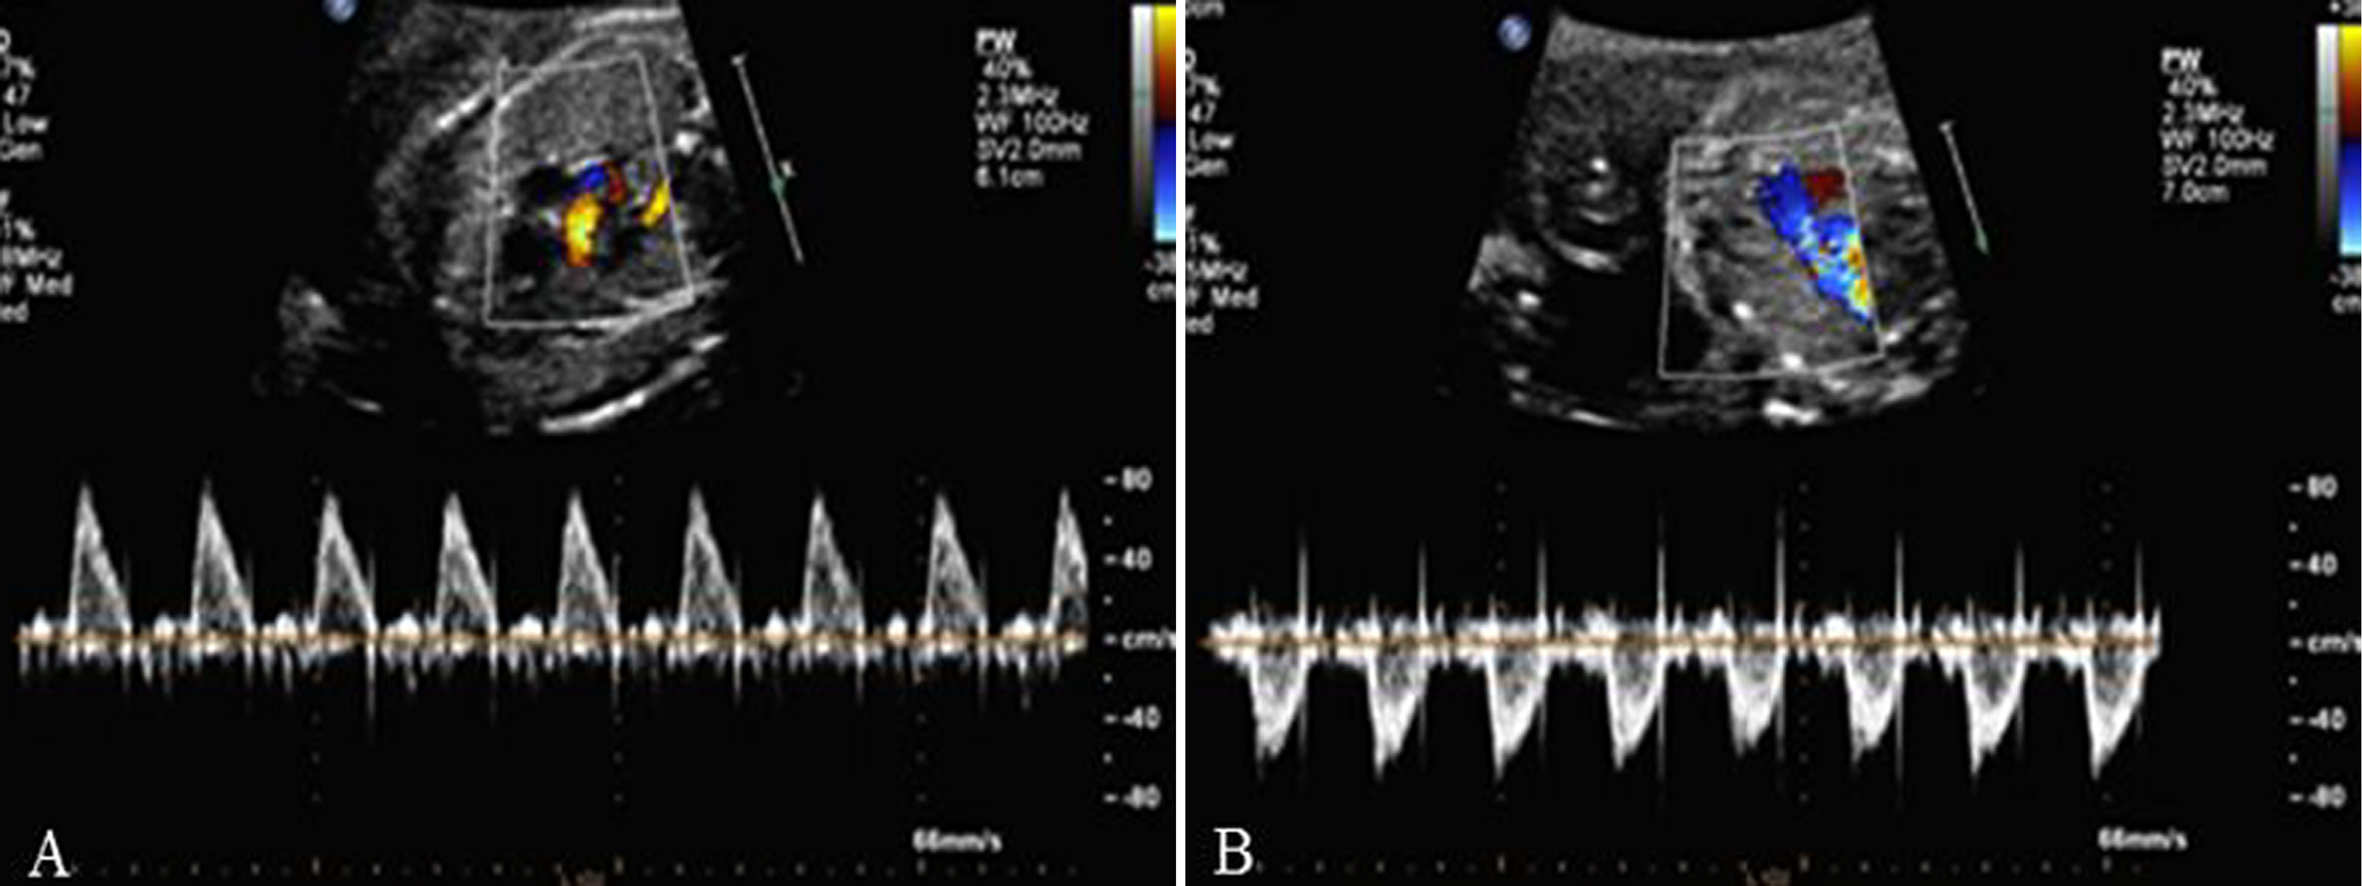

1.主动脉(AO)瓣及AO根部 多个切面都可显示AO根部和LV相连的情况,血流显示清楚。在色彩上,AO要比肺动脉(PA)鲜艳,血流速度比PA内的血流速度快,其原因可能与AO内径较细、远端血流阻力较PA的阻力小有关(图2、图3)。

图2 左室流出道切面观(A)及血流(B)

图3 主动脉(A)及肺动脉(B)血流时间流速曲线

AO的血流频谱为窄带单峰,上升支较下降支快。由于升主动脉和主动脉弓的血液主要来自胎儿的LV,在心室的舒张期可以发现血流中断,形成有空窗的基线。

2.肺动脉瓣及PA 显示相对困难,有报道认为胎儿PA的血流显示率不足一半,并且血流速度最快的部位在动脉导管处。PA的频谱显示为非对称性的三角形,上升速度大于下降速度(图3、图4)。